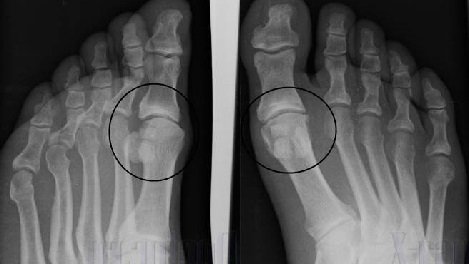

Diagnózis deformációja osteoarthritis, a láb elsősorban magában foglalja teljesítő radiológiai vizsgálatok. A fő szempontok, amelyek alapján a diagnózis, vagy:

- csökkenti a méretét a különbség az ízületi felületek;

- a jelenléte a ciszták a csontszövet;

- egyre subchondral csontsűrűség, amely fokozatosan halad;

- hiányos aztán teljes a zavar a fejemben az első csont a szár.

Alapján röntgen vizsgálat is jelzi a szintet deformáló osteoarthrose. Meg kell határozni a további kezelés, valamint meghatározza a jelzések a műtét.

Fotó az arthrosis az x-ray. Szövődmények